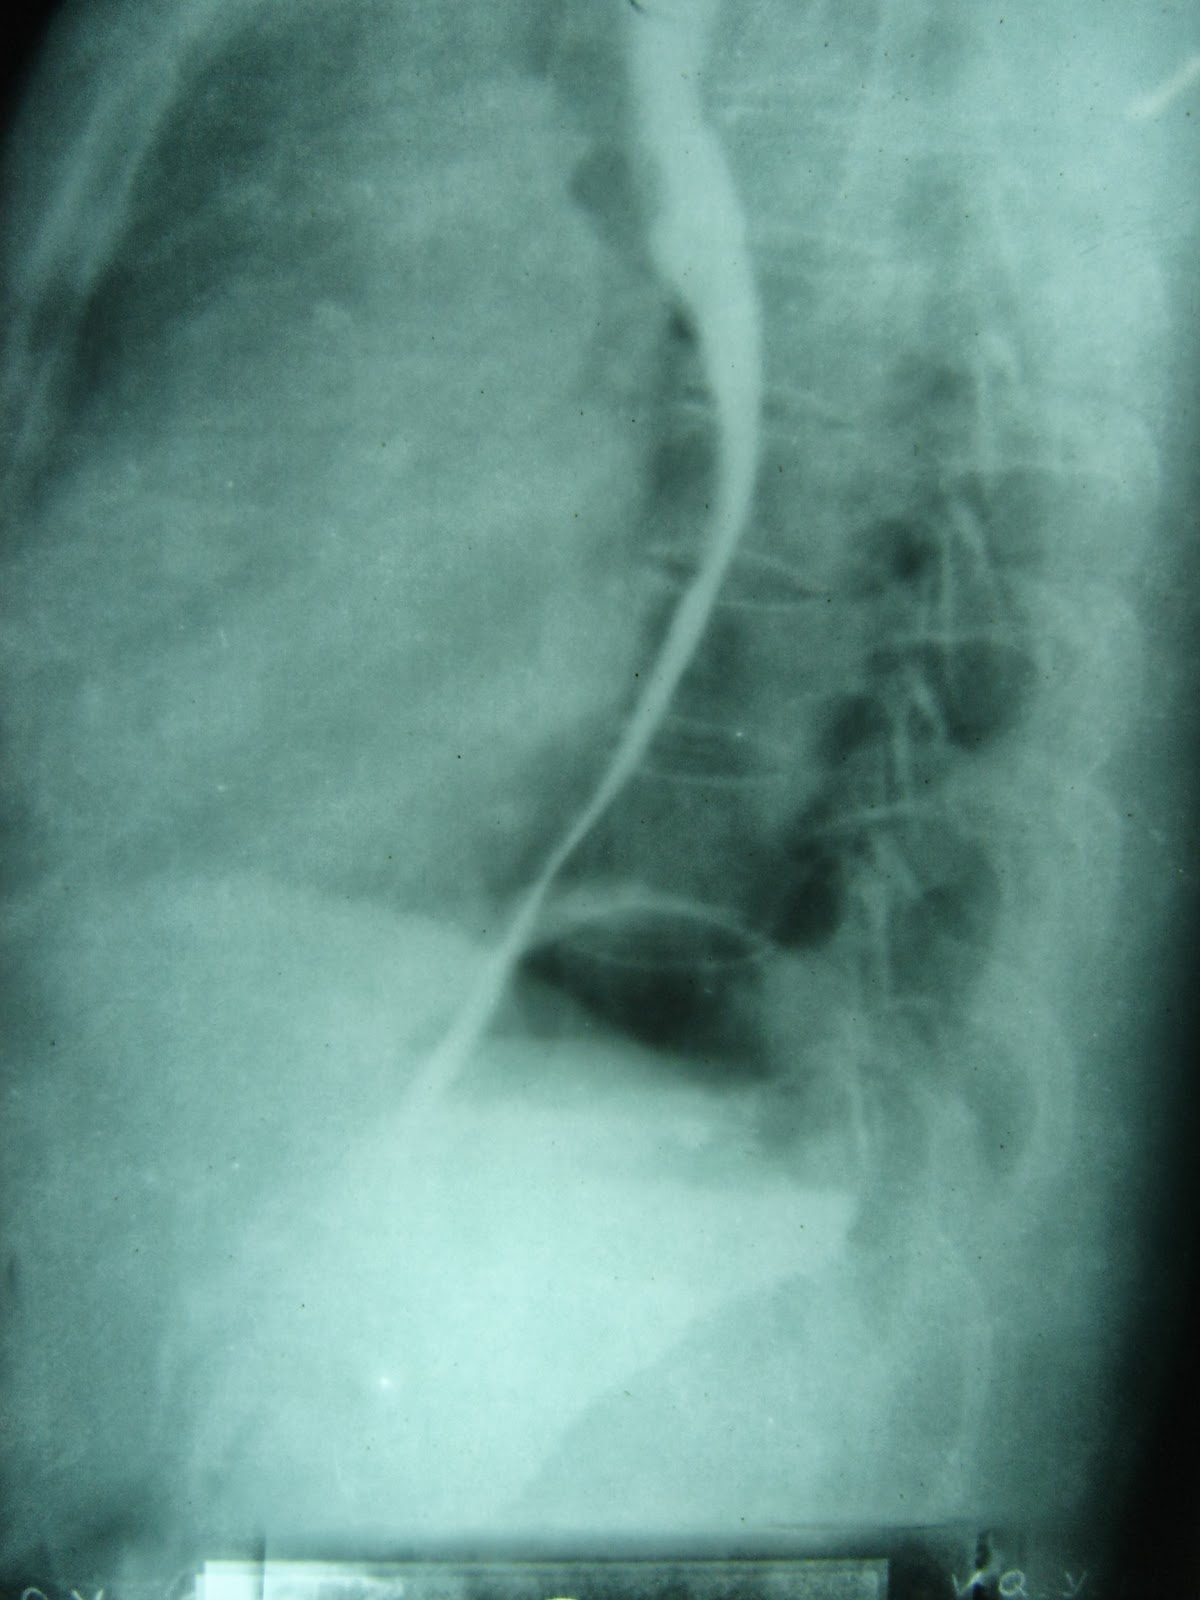

Cas lâm sàng này được 1 bạn là thành viên của Group CNKT y khoa nhờ giúp đỡ. Câu hỏi Bệnh nhân nữ 79 tuổi, tức vùng thượng vị lan lên cổ, HA: 60/40mmhg. Các bác xử trí sao ạ. Link Bài viết gốc tại Group Cập nhật kiến thức y Khoa Trả lời Những comment có giá trị. Theo Bs Phạm Minh : Bệnh nhân này check xem suy tim không, đang dùng thuốc gì. hình ảnh này gợi ý ngộ độc digoxin, Bệnh nhân có tiền sử bệnh tim 2 năm nay, lâu lâu lên cơn mệt, người đồng bào, không dùng thuốc gì ở nhà ạ! Siêu âm tim Ef 32%. Huyết áp lúc mới nhập viện: 100/60 Cũng theo Bs Minh thì: nghĩ kali có giảm. 1 bù kali 2 cho mgs04 nếu là anh xử trí Kali 3,7 mmol anh ạ! Em mới pha nor liều thấp và cho truyền dịch chậm. Hình ảnh xem tại D1. Chờ xét nghiệm men tim. Bs Minh tiếp tục truy vấn: dùng nor rồi e có nghĩ dùng gì để xóa PVC không ? Và phân tích tiếp: các nguyên nhân có thể gây PVC nhịp đôi: thiếu máu cục bộ sau nhồi máu cơ tim, ngộ độc digoxin, hạ kali, hạ magne, dùng chủ...